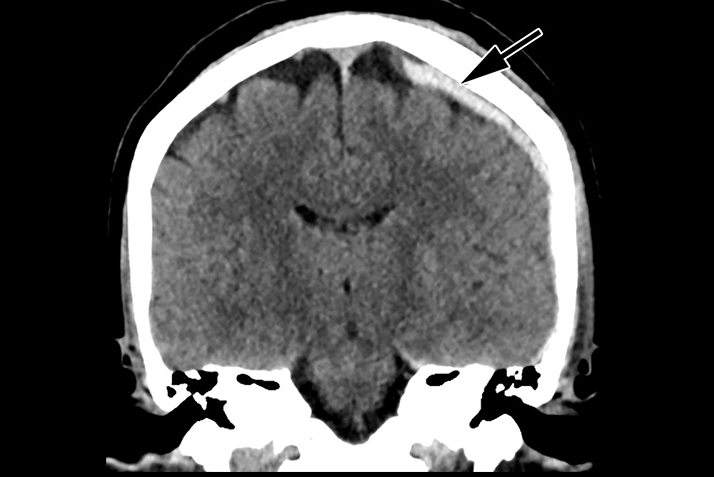

A 42-year-old woman with a history of “hit by boyfriend.” (A) Frontal and (B) lateral radiographs of the left forearm show a nondisplaced fracture of the mid-diaphysis of the ulna (wide bold arrows). There is an old healed fracture of the distal radius with hardware. Images courtesy of the Journal of the American College of Radiology.Further analysis of the cases of domestic violence indicates that nondisplaced fractures of the ulna were telltale signs of abuse: 95% of women who were victims had nondisplaced isolated ulnar fractures, compared with 43% of women who were not victims.